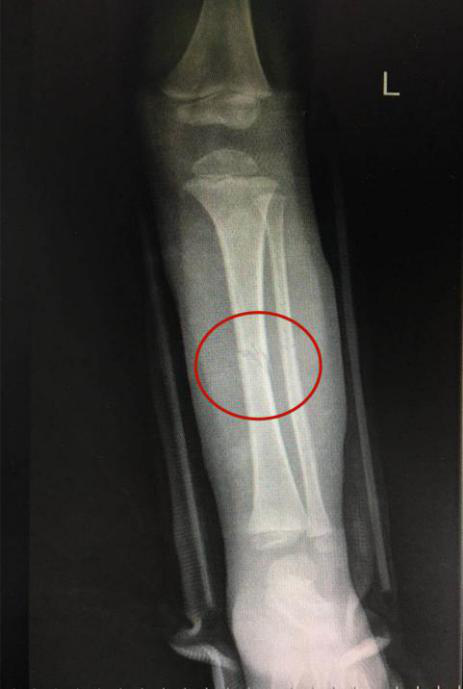

經(jīng)當(dāng)?shù)蒯t(yī)院照X光顯示,橦橦左脛腓骨中段骨折,建議全身麻醉下行彈性髓內(nèi)釘手術(shù)。

接診的瀘州市中醫(yī)醫(yī)院骨傷一科副主任中醫(yī)師李孟澤查看了患兒之前的X光片及左下肢情況,發(fā)現(xiàn)其骨折移位較大(骨折處彎曲呈30度角以上),導(dǎo)致左下肢中段嚴(yán)重畸形。

手法復(fù)位前X片顯示脛腓骨斷端,左下肢中段嚴(yán)重畸形